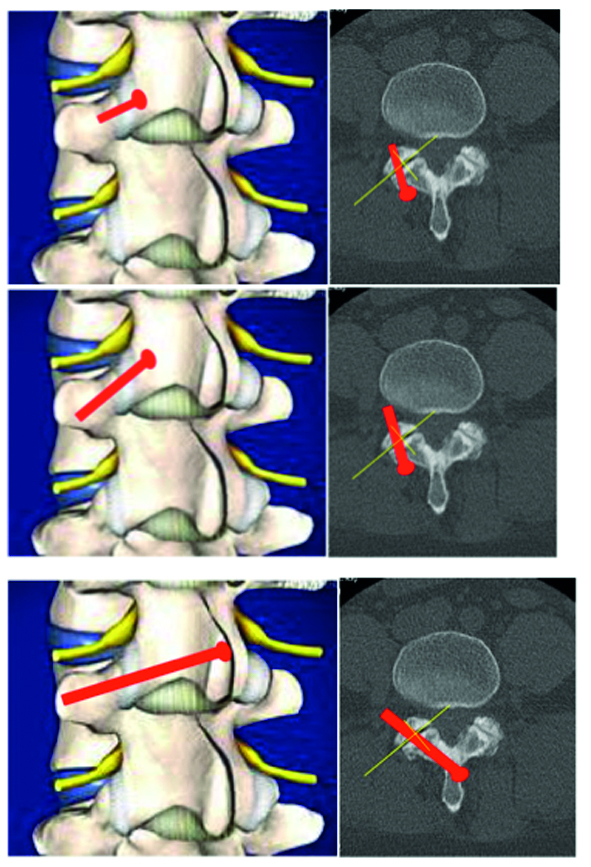

Multilevel facet pathology is shown in Fig 6. Intraoperative and postoperative images are shown (Fig 7-9).